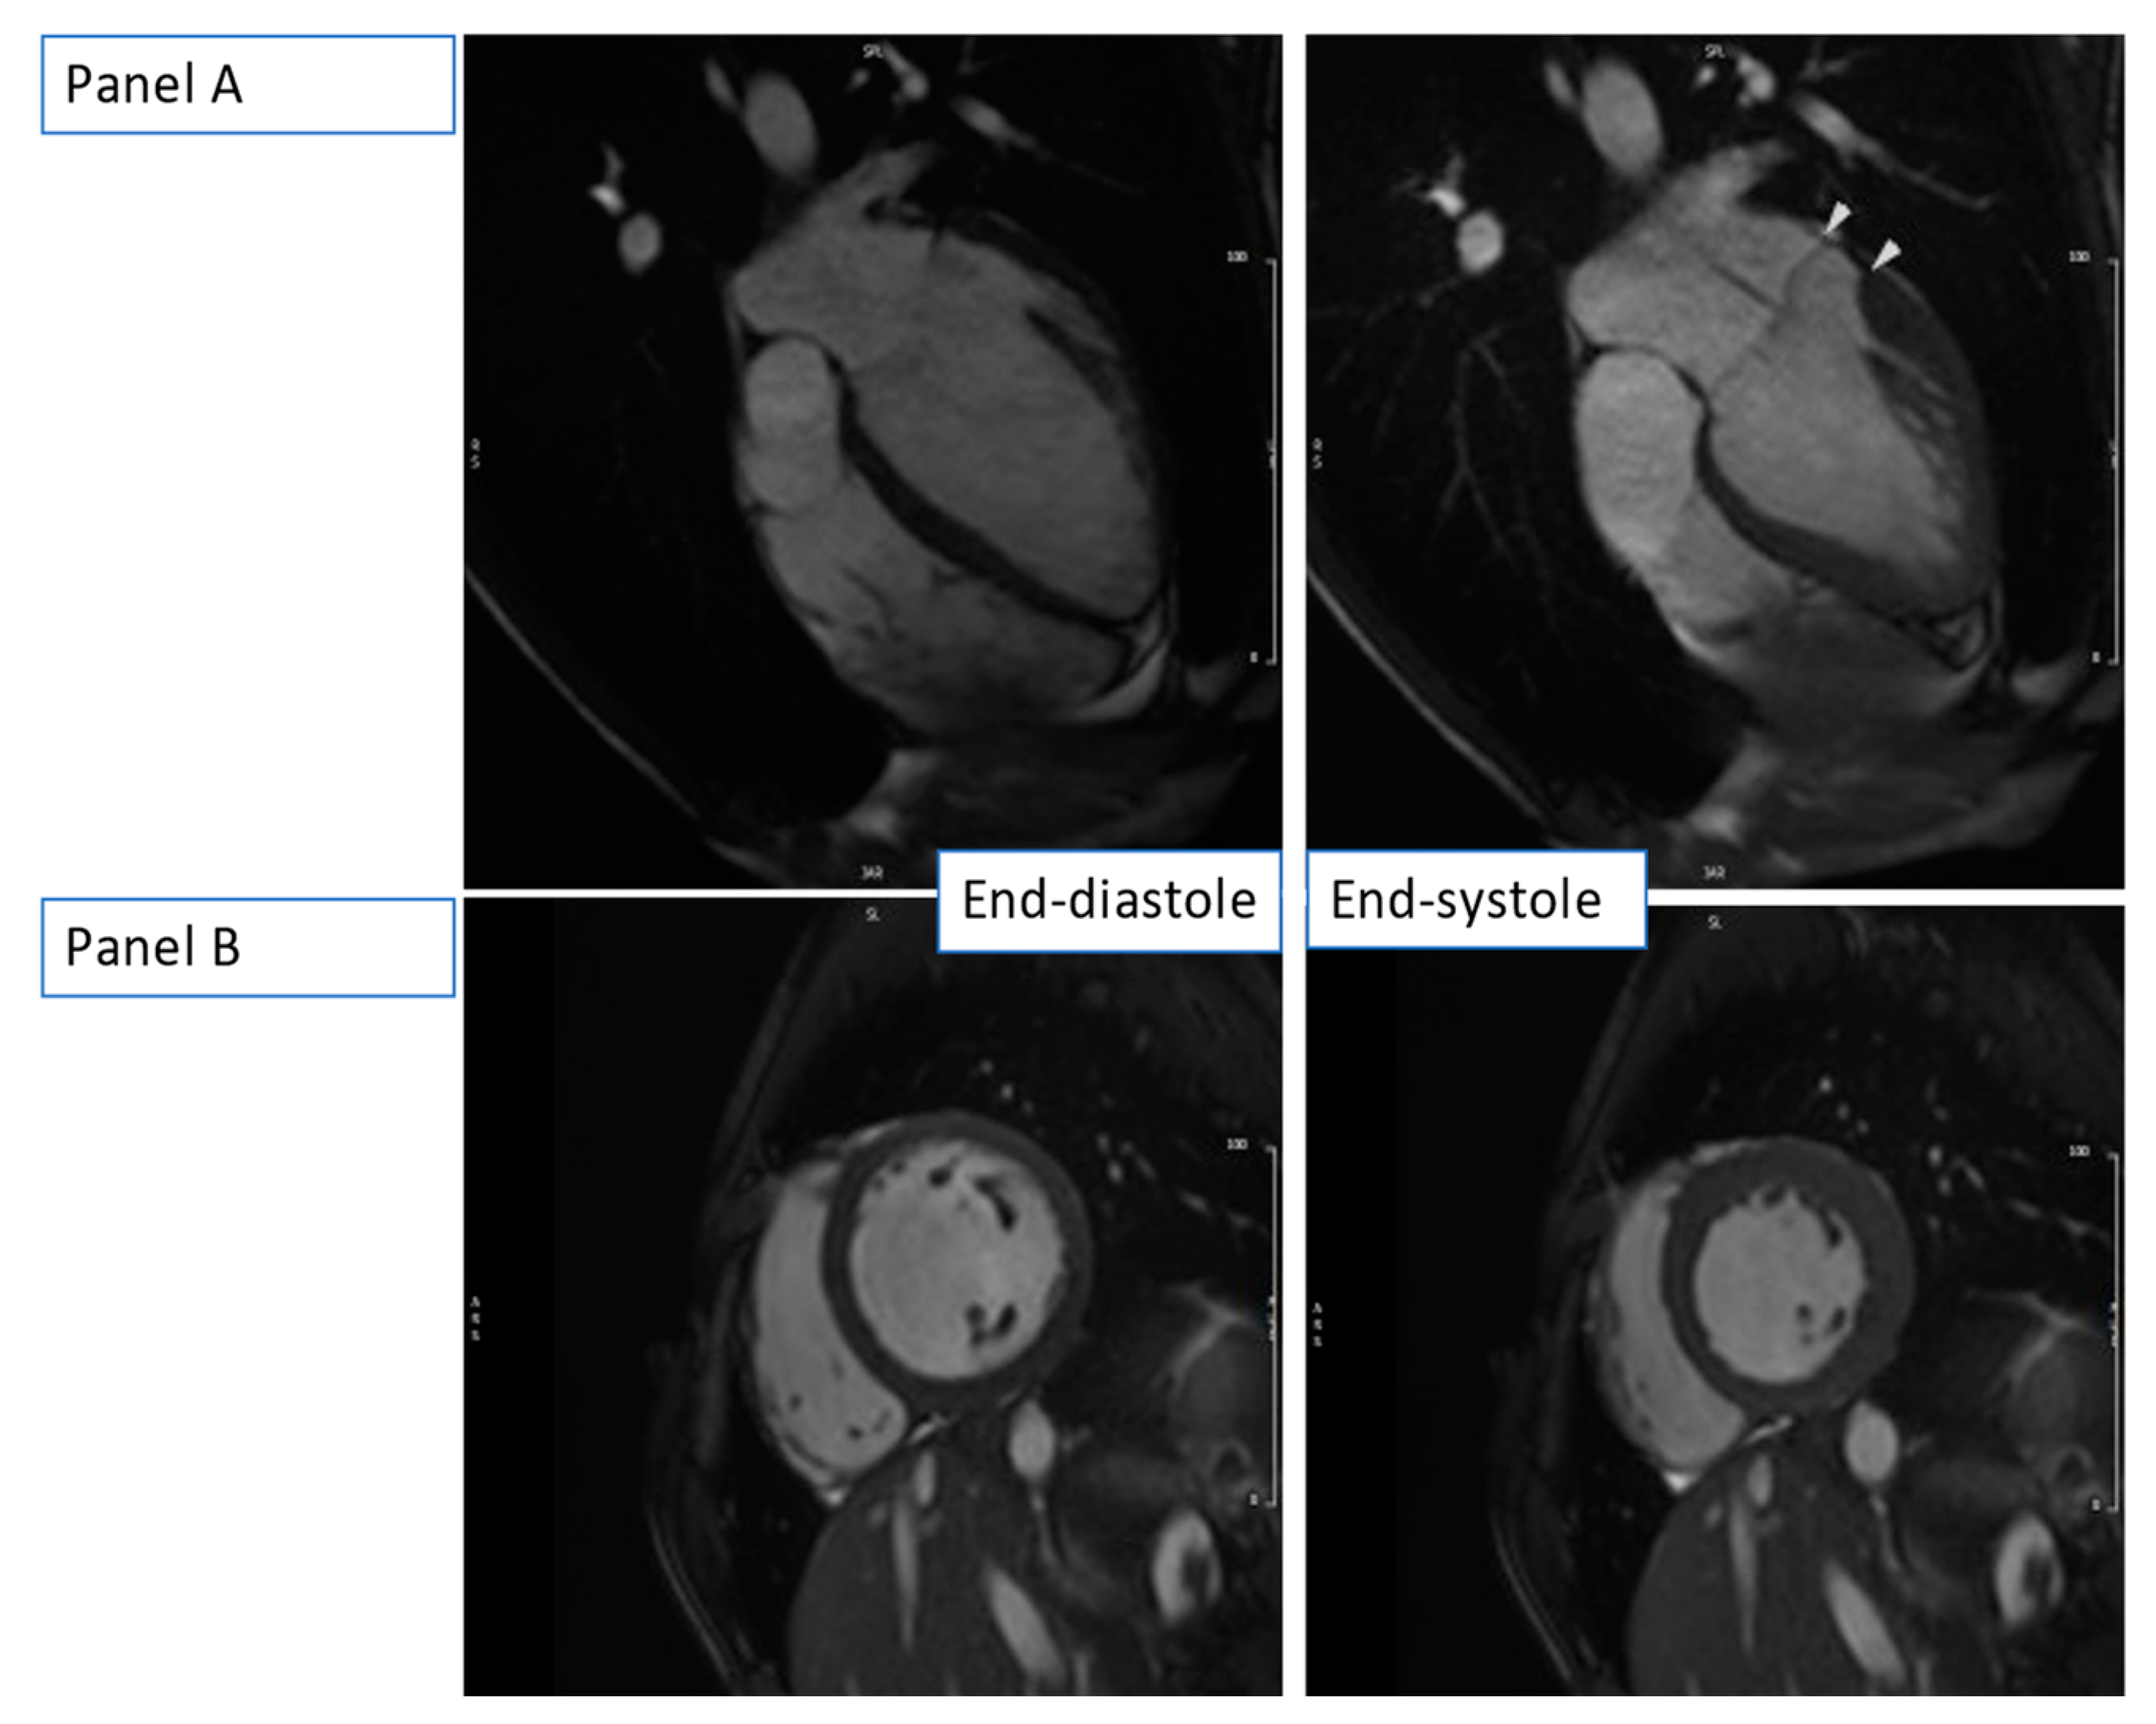

CMR confirmed the dilation of the aortic root (36 mm, z-score of 3.65) (Figure 6, Video S6) and the presence of mitral valve prolapse with only mild end-systolic regurgitation (regurgitant fraction < 5%). Yet, there was significant MAD (approximately 11 mm) and signs of increased mechanical tethering of the sub-valvular apparatus (hypokinesia of the posteromedial papillary muscle). The LV was globular and mildly dilated with a severely reduced ejection fraction (LVEF 32%). Diffuse hypokinesia was noted, more prominent on the septum, which appeared to be thinned and almost akinetic. There was no valvular disease (no aortic regurgitation, only mild mitral valve regurgitation) to justify the severity of the LV dilatation and systolic function impairment.

Figure 6. b-SSFP still images at end-diastole (left-sided images) and end-systole (right-sided images) showing dilated LV with severely reduced ejection fraction in the absence of volume load from valvular dysfunction. (Panel A): HLA view at end-diastole and end-systole with arrows showing MAD. (Panel B): Short-axis basal slice at end-diastole and end-systole.